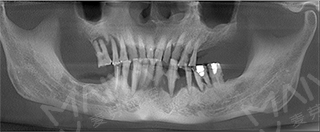

经过先进的CT拍摄发现,麦芽口腔种植医师团队指出,由于长期对口腔疏于护理,李老的牙周情况非常差,余牙松动,且牙槽骨萎缩、吸收,现存骨量无法进行传统的种植牙术式。

老李种植前全景片检查